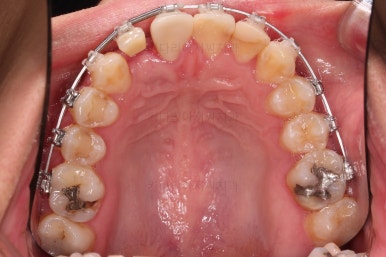

임플란트를 위한 기본 셋팅이 거의 완료되었습니다.

이 모습까지 13개월 걸렸네요.

굉장히 급한 마음으로 달려왔습니다.

지금부터는 임플란트, 보철 등을 진행하며 연산동치아교정은 보조적으로 진행하게 됩니다.